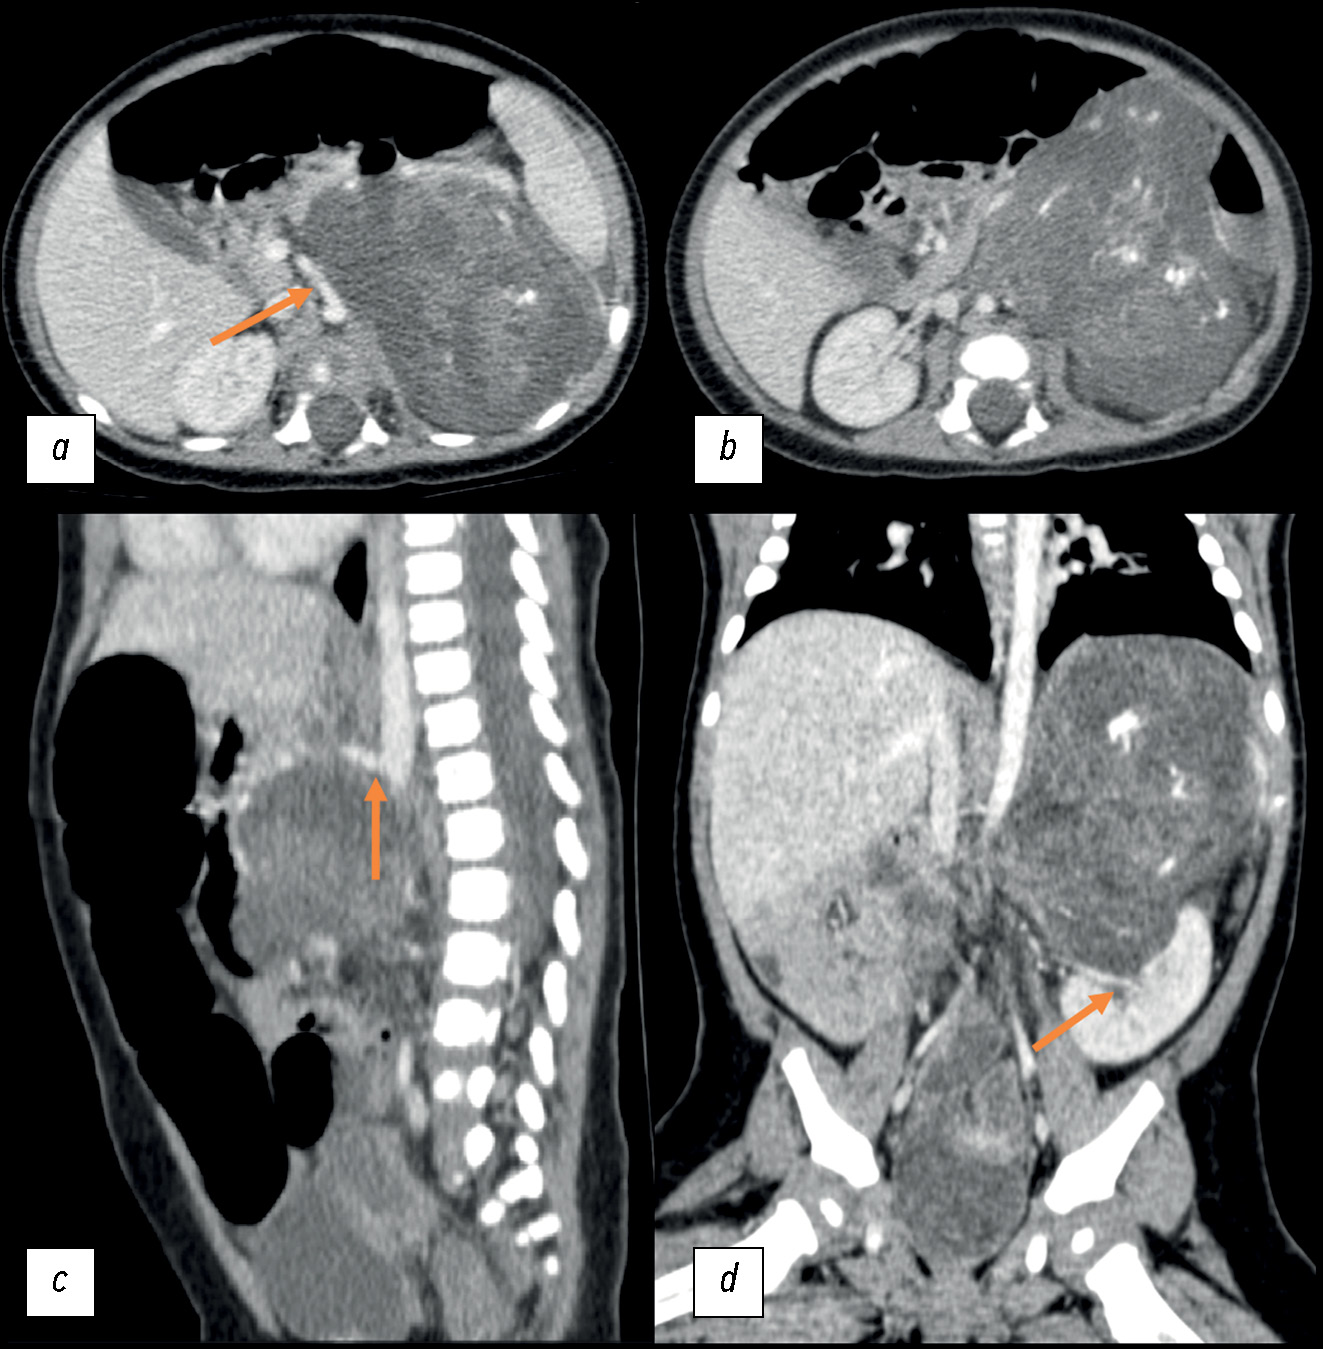

Role of artificial intelligence and novel visualization techniques in the early diagnosis of pancreatic cancer: a review

Abstract

Pancreatic ductal adenocarcinoma is the most common pancreatic cancer. It is characterized by a progressive course or distant metastases in 80%–85% of cases. Despite advances in understanding of pancreatic ductal adenocarcinoma, the disease is consistently linked to poor prognosis due to late diagnosis and limited treatment options in advanced stages. Recently, image processing using artificial intelligence has been introduced for pancreatic ductal adenocarcinoma diagnosis and demonstrated promising results. This review summarizes current scientific data, evaluates the role of artificial intelligence in imaging and early detection of pancreatic ductal adenocarcinoma, and identifies issues that warrant further investigation. The search for publications was conducted using PubMed, Google Scholar, and eLibrary. The following Russian and English search keywords were used: ранняя диагностика рака поджелудочной железы (early diagnosis of pancreatic cancer), искусственный интеллект (artificial intelligence), протоковая аденокарцинома поджелудочной железы (pancreatic ductal adenocarcinoma), медицинская визуализация (medical visualization), наночастицы (nanoparticles), pancreatic cancer, artificial intelligence, early diagnosis pancreatic ductal adenocarcinoma, and pancreatic cancer imaging. Significant progress in early detection of pancreatic ductal adenocarcinoma using artificial intelligence technologies was observed. Current approaches include pre-imaging risk stratification and increased data volume by analyzing electronic medical records. Despite substantial achievements, the clinical implementation of artificial intelligence technologies remains challenging. The use of artificial intelligence along with biomarkers is a promising direction and may enhance theranostics of various malignancies, including pancreatic ductal adenocarcinoma.

317-330